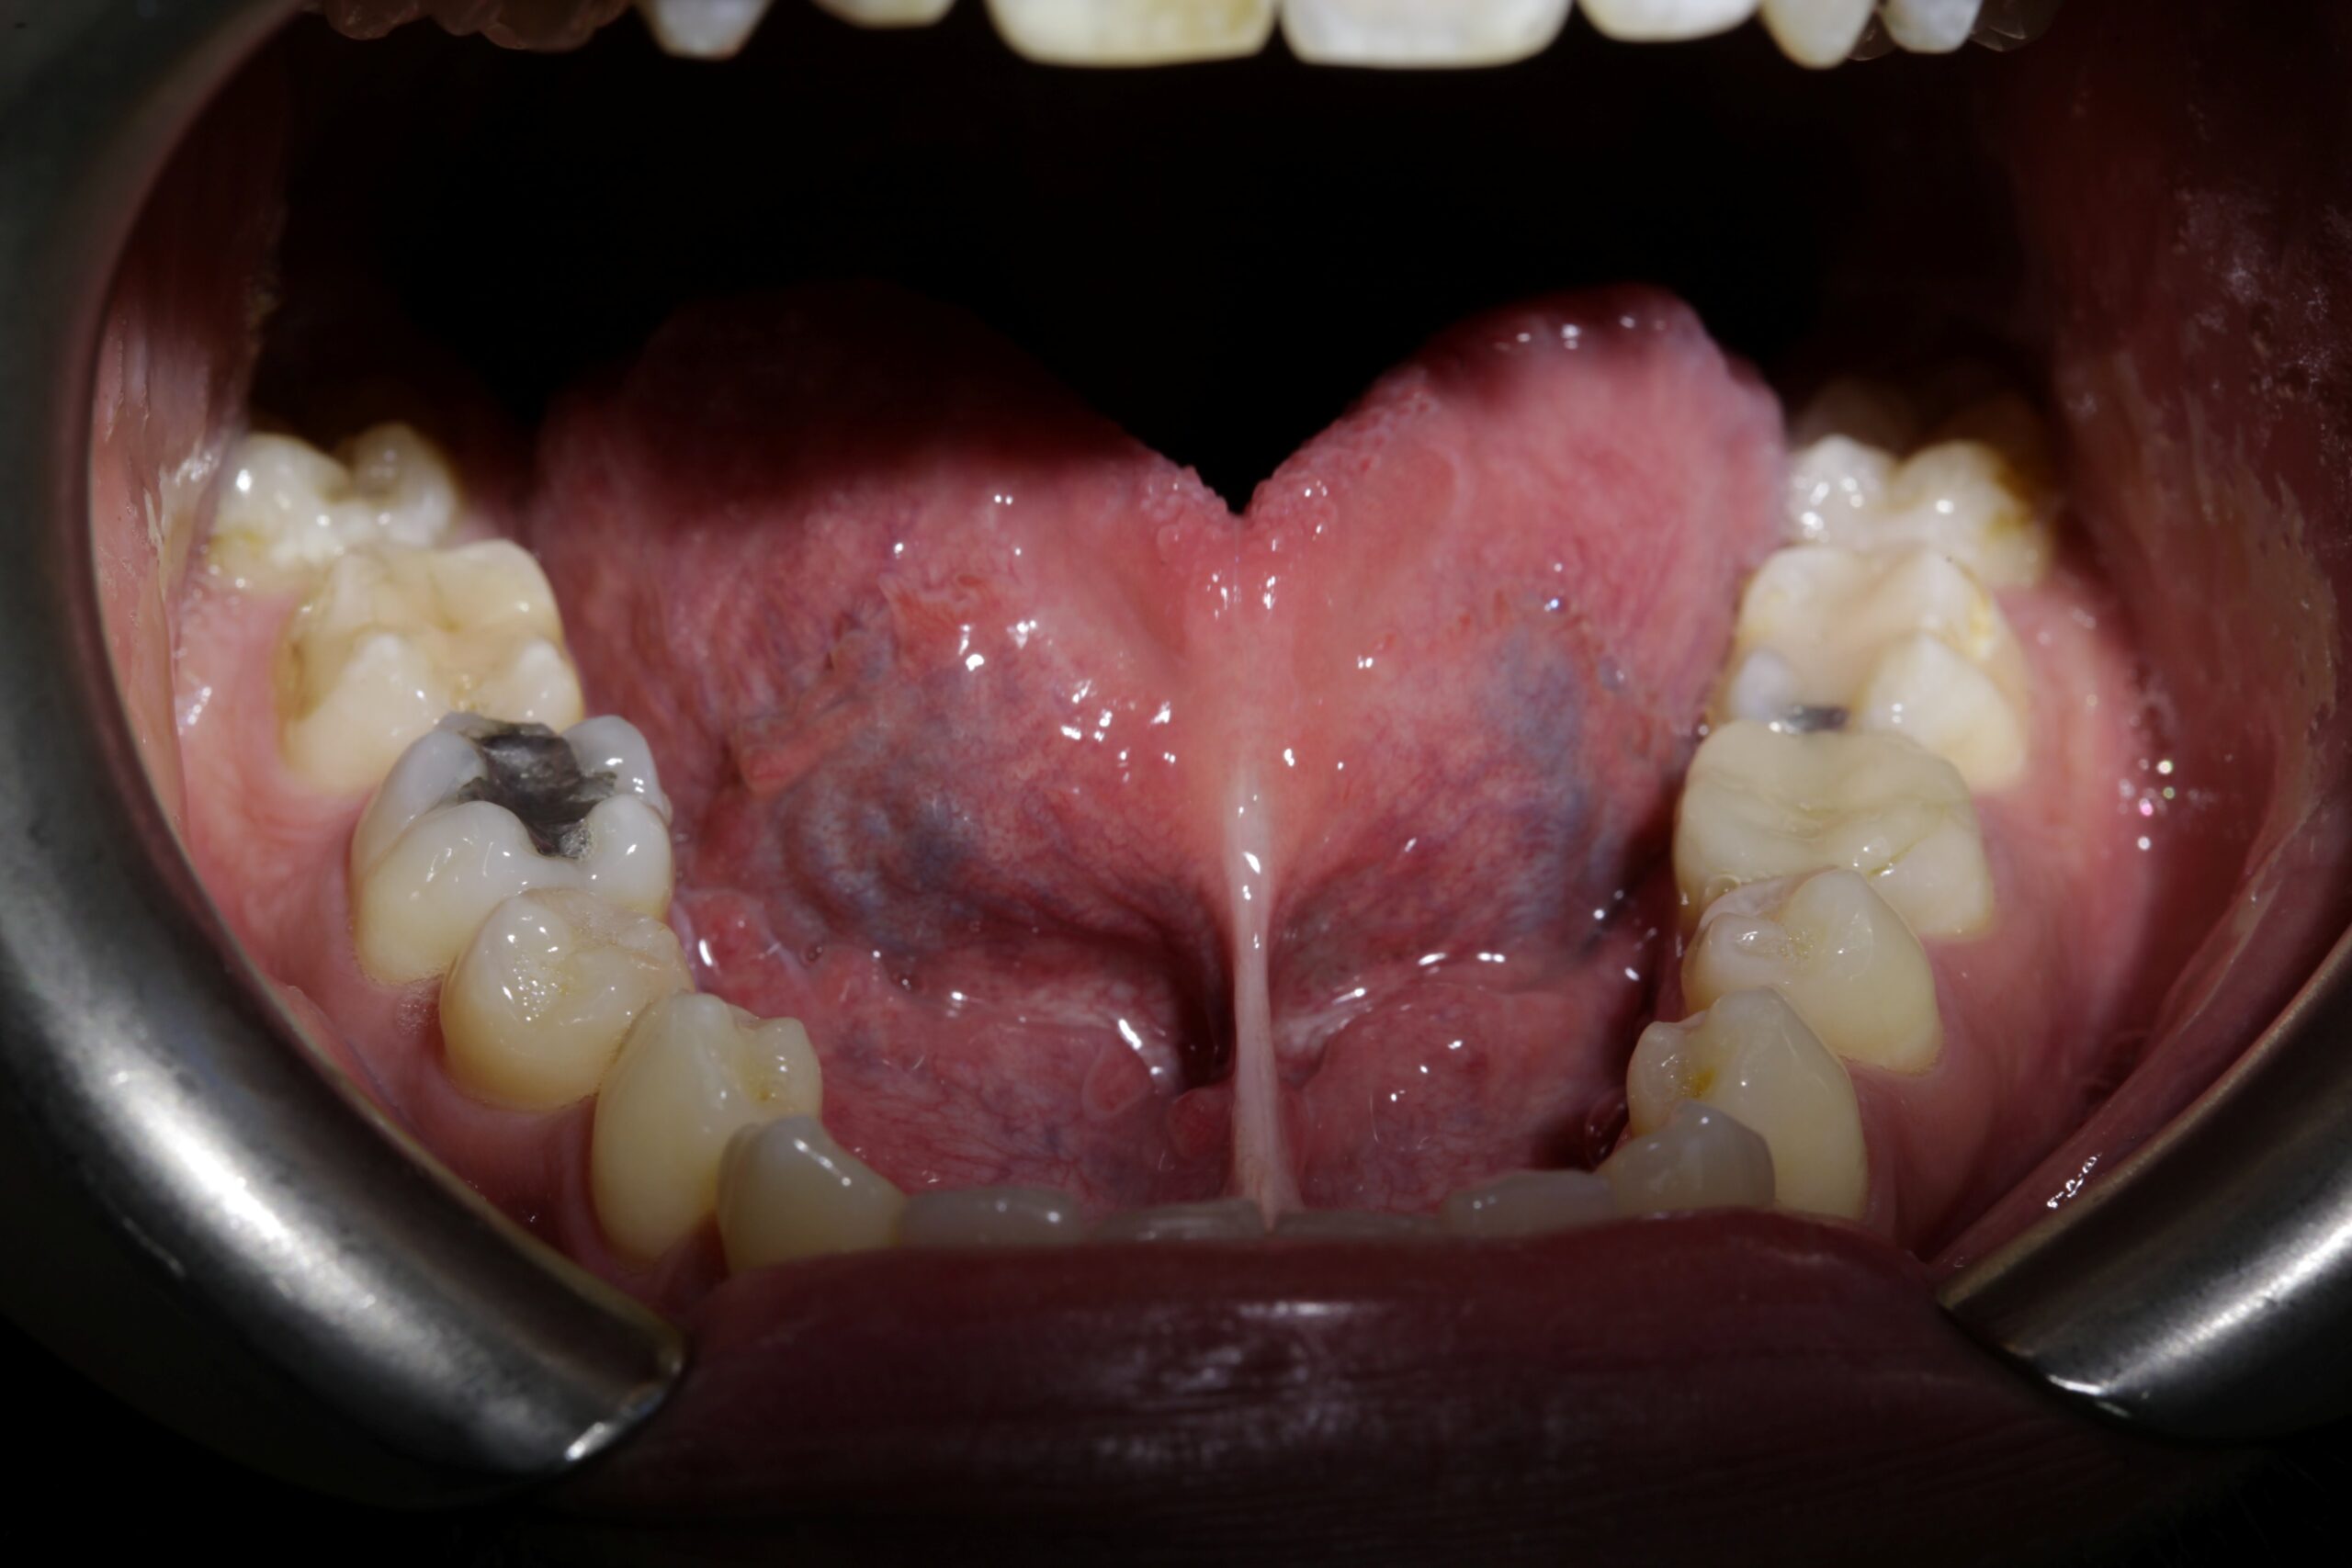

Release of tongue tie with Biolase Laser Technology